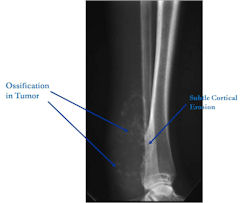

Radiographic Presentation

Plain X-Rays:

- Broad based mass on surface of bone that is partially mineralized (fluffy calcifications/ossification in mass)

- Appearance similar to periosteal osteosarcoma but usually with more ossification

- Matrix mineralization is similar to conventional osteosarcoma with cloudlike opacities

- Amount of mineralization varies

Codman’s triangle/Malignant periosteal reaction may be present

- Cortical erosion is usually evident

- Medullary cavity is usually uninvolved

Fig. 1 Plain X-Ray: High Grade Surface Osteosarcoma of Distal Tibia